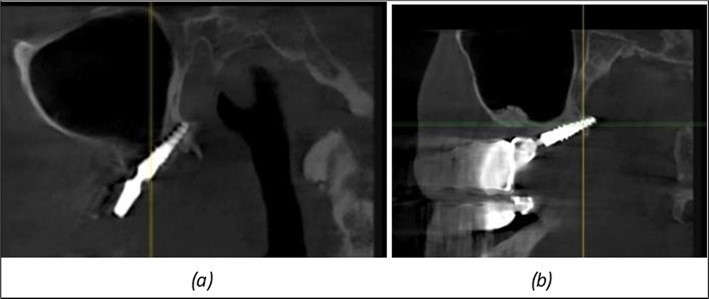

Figure 9.Implants in the pterygoid plateau area: (a) TPG implant fixed in the maxillary-sphenoid junction area, quadrant 1; (b) TPG implant fixed in the maxillary-sphenoid junction area, quadrant 2.

Implants in the pterygoid plateau area: (a) TPG implant fixed in the maxillary-sphenoid junction area, quadrant 1; (b) TPG implant fixed in the maxillary-sphenoid junction area, quadrant 2.